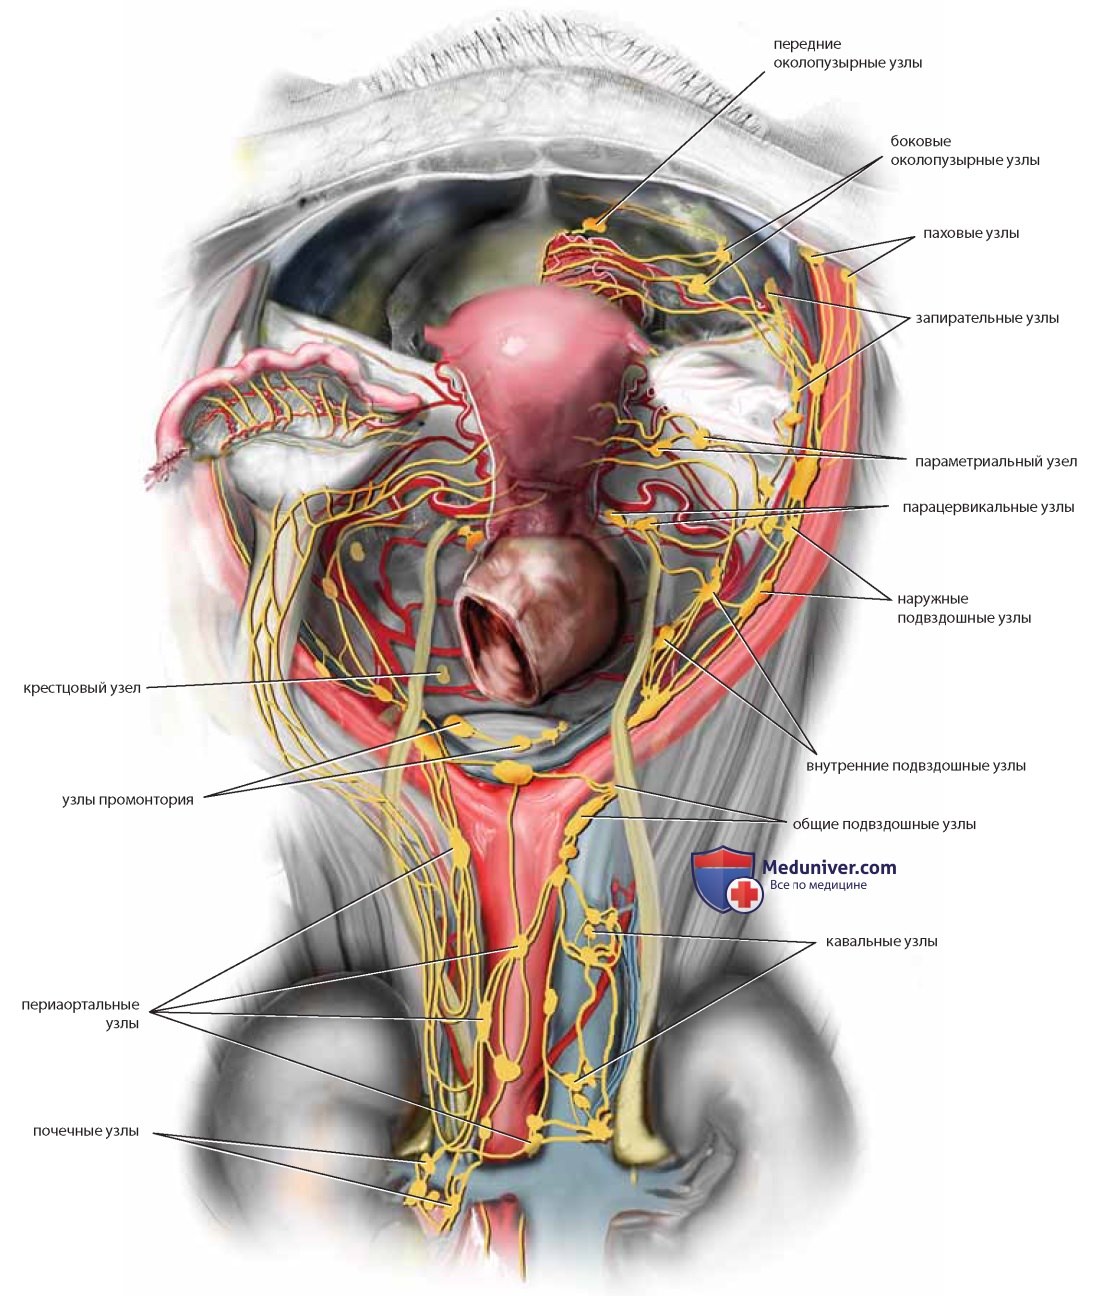

Анатомия малого таза: детальные схемы и изображения